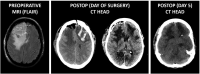

SARS-CoV-2 infection is associated with hypercoagulability, heparin resistance, and increased perioperative mortality and morbidity. Recommendations on screening and postponement of elective surgery after SARS-CoV-2 infection are being relaxed worldwide. We present a case of fatal thrombotic complication in an asymptomatic incidental SARS-CoV-2 infection (Omicron BA.5.2 variant, first isolated in May 2022) in a triple-vaccinated patient undergoing elective resection of frontal meningioma. The assumption that asymptomatic infection with more recent SARS-CoV-2 variants does not add any perioperative risk remains to be demonstrated. Based on the presented case of unexpected fatal thrombotic perioperative complication in a triple-vaccinated, asymptomatic BA.5.2 SARS-CoV-2 Omicron infection, it would seem prudent to continue to screen for asymptomatic infection and to systematically audit perioperative outcome. Evidence-based perioperative risk stratification of elective surgery in asymptomatic patients with Omicron or future COVID variants relies on reporting of perioperative complications and prospective outcome studies, which would rely on continued systematic preoperative screening.